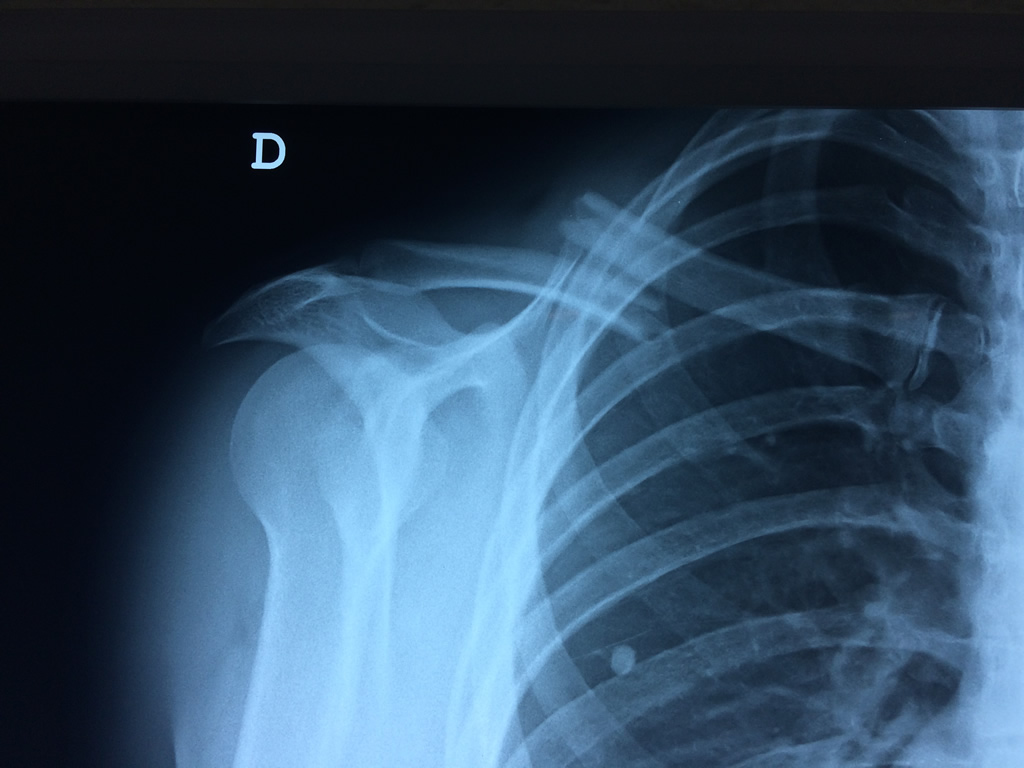

Húmero - Clavícula

La clavícula es un hueso largo, con forma de "S" itálica, situado en la parte anterosuperior del tórax. Junto con la escápula forman la cintura escapular. Se puede palpar por toda su longitud y se extiende del esternón al acromion de la escápula, siguiendo una dirección oblicua lateral y posterior.